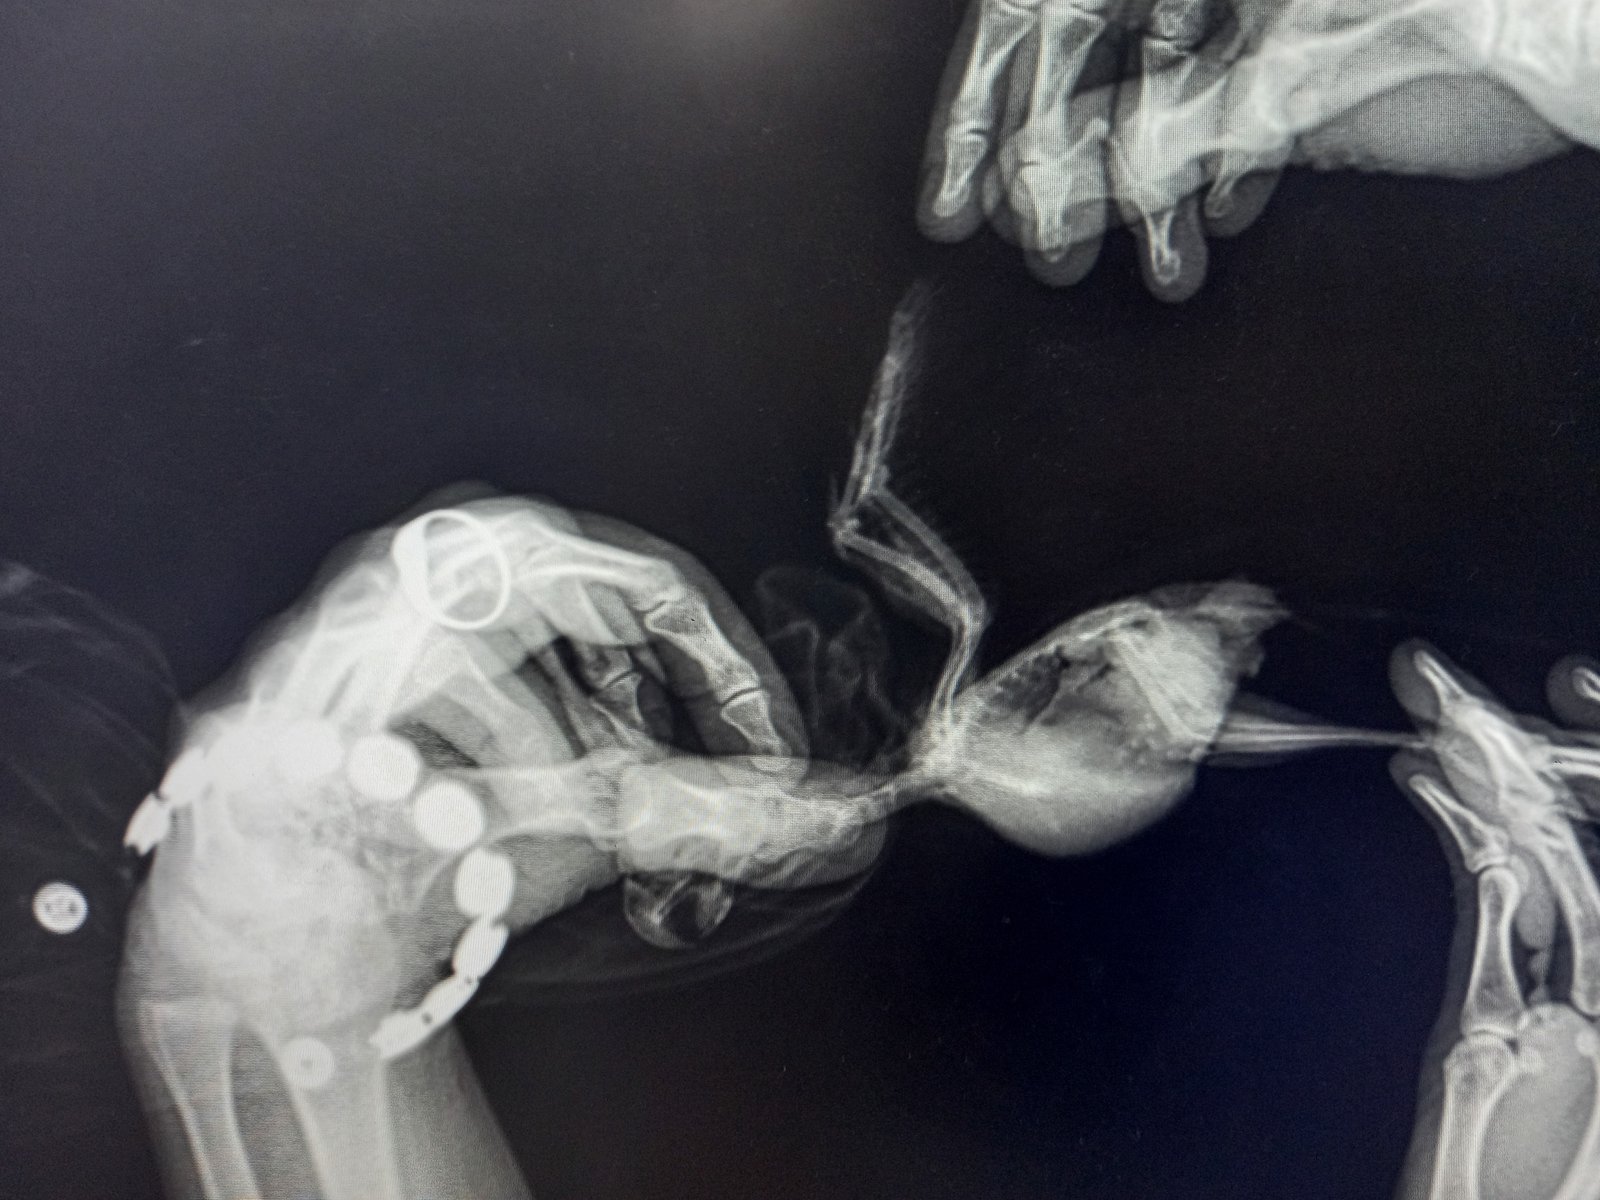

Добрый день! Мне отдали какарика, у предыдущих хозяев он пробыл месяц, им его тоже отдали. Пол и возраст не знаю. Птица хрипит и свистит при дыхании, иногда вроде бы как чихает. Выделений из ноздрей нет. При этом ест хорошо, любит купаться. Я так понимаю, что такое состояние у него больше месяца. Никогда не чирикает. Летает плоховато, но это может быть из-за того, что всегда жил в тесной клетке, хвост обломан. Делали рентген, но врач сказал, что птица мелкая и ничего не видно. Понимаю, что его надо лечить, но вот чем и от чего... Помогите, плиз.

20211018_112811.jpg

20211018_112706.jpg

20210913_124626.jpg

Забыла написать - иногда хвост дергается и пульсирует в такт дыханию.